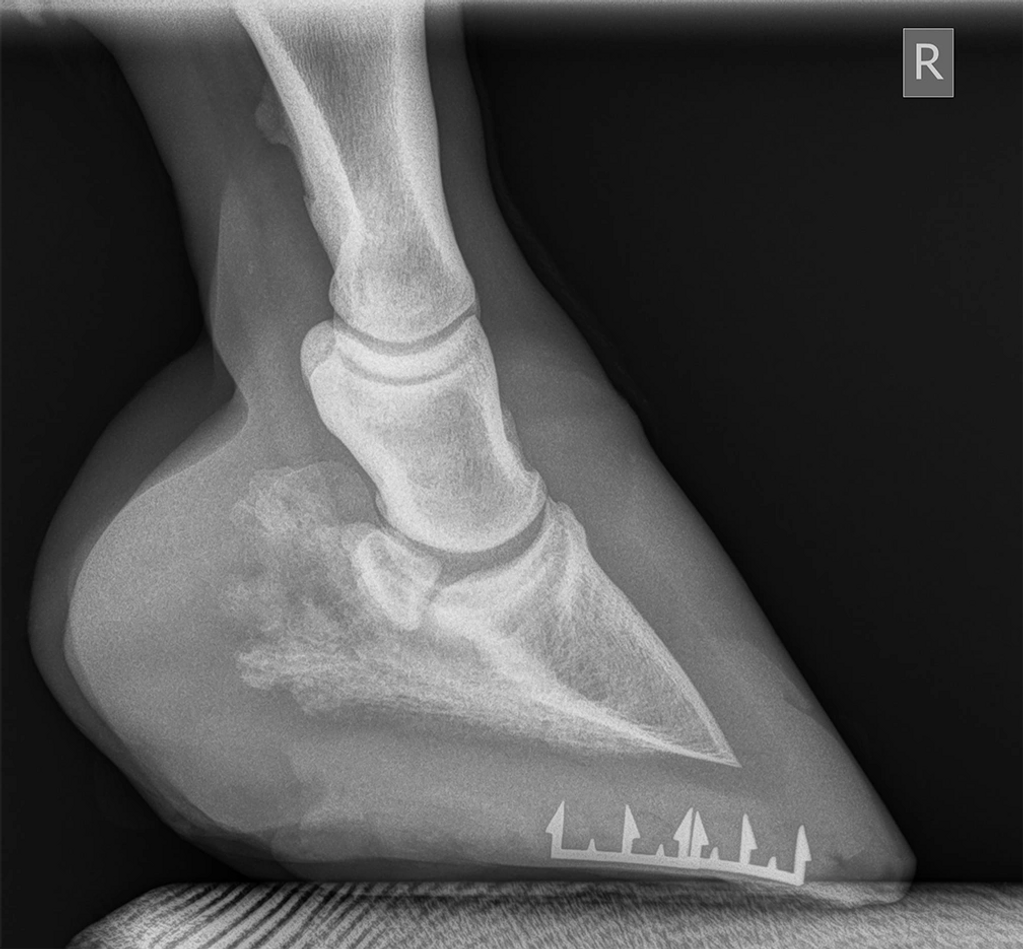

The Gypsy Vanner was barefoot, severely lame. Cracks and bacteria were more than halfway up the hoof inside. Example shown is the left front. Shoes and DE HoofTaps applied. Third cycle shows good improvement. We will continue with

DE HoofTaps until crack is completely healed.

He is now sound.